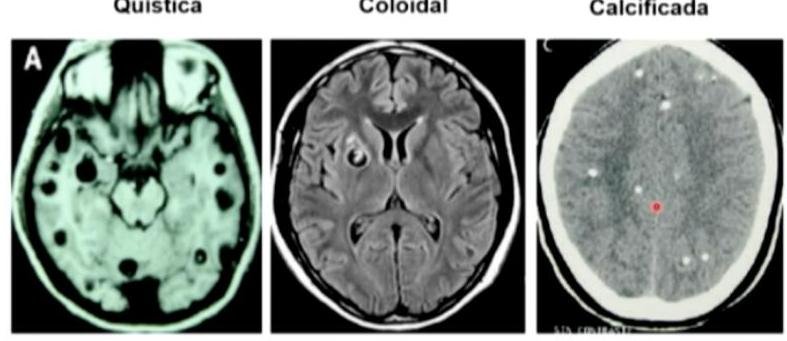

# PARASITOSIS ## DEFINICIÓN **Infecciones intestinales** generadas por **parásitos** en el ser humano, con clínicas variables y poco específicas hasta cuadros **asintomáticos**, sobre todo en adultos; prevalentes en zonas tropicales y con poca higiene debido a contaminación de alimentos o **ingesta directa**. ## EPIDEMIOLOGÍA * La frecuencia en México fluctúa del 2-39 %. * La infección por **Giardia lamblia** es el parásito entérico más frecuente a nivel mundial. * Se calcula que hay 9 millones de infectados por **Giardia lamblia** en México. * También es la más frecuente en ganado, perros y gatos. ## CUADRO COMPARATIVO | | GIARDIASIS | AMEBIASIS | TENIASIS | CISTICERCOSIS | | :--: | :--: | :--: | :--: | :--: | | AGENTE | Giardia lamblia | Entamoeba histolytica | Taenia solium (forma madura) | Quistes larvarios de Taenia solium | | CLÍNICA | Sintomática en niños<br>Diarrea aguda y crónica<br>**Síndrome de Malabsorción**<br>Pérdida de peso | Frecuentemente asintomática<br>Diarrea con moco y sangre (**Disentería**)<br>Puede haber **Abscesos Hepáticos**<br>**Amebomas** (tumores en el ciego) | Dolor abdominal y disminución del apetito.<br>Pérdida de peso.<br>Eliminación de **proglótides** por las heces. | **NEUROCISTICERCOSIS**<br>Cefalea, náusea, vómito.<br>Lesiones ocupantes (**alteraciones visuales**, **ataxia**)<br>Muerte de **quistes** en SNC: **Convulsiones** por respuesta tisular intensa | | DIAGNÓSTICO | 1. **Coproparasitoscópico** en serie de 3<br>2. **Antígeno Fecal** de Giardia en heces.<br>3. Endoscopia o **Entero-Test** | 1. **Examen directo al fresco** de heces.<br>2. **Coproparasitoscópico** | **Coproparasitoscópico** con visualización de **huevos** o **proglótides** | **RM** o **TAC** de cráneo con lesión con **realce en anillo**, **calcificaciones** o **hidrocefalia**. | | TRATAMIENTO | - **Metronidazol** | - **Metronidazol** | - **Praziquantel** | - **Albendazol** (**Neurocisticercosis**)<br>- **Praziquantel** (Cisticercosis sin neuro) | # GIARDIASIS ## DEFINICIÓN Es una enfermedad parasitaria de distribución geográfica cosmopolita, causada por el protozoo **Giardia lamblia**, que frecuentemente ocurre en niños y se caracteriza por el desarrollo de cuadros enterales agudos y crónicos, de intensidad variable y que puede ocasionar un **Síndrome de Malabsorción Intestinal**; en los adultos es comúnmente **asintomática**. ## ETIOLOGÍA Es un protozoo flagelado, mundialmente distribuido, con mecanismos de adaptación que le permiten sobrevivir a condiciones ambientales que de otro modo lo destruirían. Experimenta una variación antigénica a nivel intestinal, lo que le permite un cambio continuo de antígenos de las proteínas de superficie, inhibiendo el reconocimiento por el sistema inmune huésped. **LA FORMA INFECTANTE SON LOS QUISTES** (se adhieren al intestino delgado, produciendo más quistes que posteriormente se excretan).  ## TRANSMISIÓN: * Alimentos y aguas contaminadas (suficiente que contenga **10 quistes** de Giardia). * Animales domésticos como perro o gato. * Ganado vacuno u ovino. * Transmisión sexual oroanal. ## EPIDEMIOLOGÍA * La prevalencia mundial varía desde 1-72 %, dependiendo de la región. * El pico de enfermedad ocurre desde el inicio del verano hasta el inicio del otoño. ## FACTORES DE RIESGO * Población pediátrica (afecta mayormente a preescolares y escolares). * Estancias infantiles. * Viaje a zonas endémicas. * Mala higiene de manos. * Sexo oroanal. * Déficit selectivo de IgA. * Hipogamaglobulinemia. # CLÍNICA Curso **asintomático** desde un 9-57%. ## SÍNTOMAS DIGESTIVOS * **DOLOR ABDOMINAL** (el más común, puede presentarse solo o asociado a otros síntomas). * Considerar sospechoso si tiende a ser recurrente. * Diarrea (aguda o persistente). * Vómito. * Meteorismo. * Distensión abdominal. * Disminución del apetito. * Síndrome de Intestino Irritable. * Fatiga crónica. ## IMPACTO NUTRICIONAL * La Giardiasis afecta la nutrición de los niños debido a un **síndrome de malabsorción intestinal**. * **Retraso del crecimiento** en el 2º año de vida si se adquiere la enfermedad en etapas tempranas. * Disminución sérica de **hierro**, **zinc** y **magnesio**. * **Pobre función cognitiva**. ## OTROS HALLAZGOS Se puede observar en algunos casos lesiones en la retina en forma de degeneración "en sal y pimienta". * Artritis reactiva y sinovitis. * Dermatitis alérgica. * Prurito y urticaria. # DIAGNÓSTICO ## 1ra elección: **Coproparasitoscópicos** en serie de 3. * Se deben identificar los **trofozoítos** o **quistes** en las heces. * Es el examen rutinario de muestras de heces fecales más conocido y usado. * Se realiza en 1er y 2do nivel de atención. ## SI LOS **COPROPARASITOSCÓPICOS** RESULTAN NEGATIVOS Y **PERSISTE SOSPECHA**: ## 2da elección: **Detección de Antígeno Fecal de Giardia lamblia** en heces. Se emplean técnicas de **anticuerpos fluorescentes** y **ensayos inmunoenzimáticos**. ## ESTUDIO ENDOSCÓPICO * Visualización directa con aspirado duodenal y toma de **biopsia**. * No es un estudio de rutina y se reserva para quienes han fallado el **coproparasitoscópico** y los **antígenos fecales**. * Hallazgos en la **endoscopia**: **gastritis antral**, **duodenitis**, **úlcera duodenal**. * **Histopatológico**: infiltración de **lámina propia** por granulocitos, linfocitos y células plasmáticas, **hiperplasia linfoide nodular** y **atrofia de vellosidades intestinales**. ## ENTERO-TEST * Se requiere que el paciente trague la cápsula y la cuerda. * Posteriormente se visualiza con microscopio y tinción directa posterior a obtener la cuerda. * Requiere personal experimentado y se realiza solo en el 2do nivel. ## PCR * Es un estudio muy **sensible** y **específico** y permite identificar la **morfología** del parásito. * Pocos laboratorios cuentan con este estudio y solo se realiza con fines de investigación en el 3er nivel. # TRATAMIENTO Debido a que los pacientes **asintomáticos** con infección por Giardia lamblia expulsan los quistes y se convierten en fuente de infección para su comunidad y entorno, se debe **INICIAR TRATAMIENTO EN TODOS LOS CASOS**. ## 1ra elección: **Metronidazol** * Tiene una eficacia de 60-100% en adultos y niños. * Dosis: 5 mg/kg/dosis 3 veces al día por 5 días. * Debe suspenderse si presenta intolerancia al medicamento. * Evitar alcohol por reacción **Disulfiram**: Inhibición de la oxidación del alcohol por bloqueo de la enzima aldehído deshidrogenasa, provocando una elevación de niveles de acetaldehído. ## 2da elección: **Tinidazol en monodosis** * En caso de que el Metronidazol no sea bien tolerado. * Indicado en niños de poblaciones de bajos recursos. ## ALTERNATIVAS: * **Metronidazol** + **Albendazol** (en caso de resistencia). * **Paromomicina** (indicada en 1er trimestre de embarazo). * **Secnidazol**. * **Albendazol**. * **Furazolidona**. * **Nitazoxanida**. ## PERSISTENCIA DE LOS SÍNTOMAS * Resistencia farmacológica. * Cura seguida de **reinfección**. * Falta de apego al tratamiento. * Intolerancia a la **lactosa post-giardiasis**. * Inmunodeficiencias. ## EVALUACIÓN POSTERIOR Vigilar de manera rutinaria con nuevas muestras fecales a los 3-5 días de finalizar el tratamiento. ## REFERENCIA Envío a 2do nivel: * Síntomas sugestivos de Giardia lamblia + **Coproparasitoscópico** seriados negativos. Envío a 3er nivel: * Síntomas + **Coproparasitoscópico** Negativos + **Antígeno fecal** negativo. # AMEBIASIS ## DEFINICIÓN Es una infección intestinal parasitaria, de distribución mundial y provocada por la **Entamoeba histolytica** que tiene como hábitat el intestino grueso. Su característica es que puede presentar **diseminación hematógena**, provocando un **absceso hepático**, así como **amebomas** en el colon. ## ETIOLOGÍA La **Entamoeba** presenta dos formas: **TROFOZOÍTO**: forma vegetativa invasora, plasma hialino, puede contener glóbulos rojos. **QUISTE**: Forma resistente a los antibióticos. Esférico de 10-15 micras (**ELEMENTO INFECTANTE**). ## Transmisión: * Agua y alimentos contaminados. * Fecal/Oral. * Contacto directo. * Fómites. * Transmisores biológicos. ## EPIDEMIOLOGÍA * Es más frecuente en áreas tropicales o subtrópicas. * La presentación **EXTRAINTESTINAL** más frecuente se sitúa en el **HÍGADO** (formando **absceso hepático**). ## FACTORES DE RIESGO * Contaminación fecal de agua y alimentos. * Mala higiene de manos. # FACTORES PARA FORMACIÓN DE ABSCESO: * Sexo masculino. * 3ra a 5ta década de la vida. * Alcoholismo. * Padecimientos oncológicos. * Prácticas homosexuales. * Inmunosupresión. * Habitar o viajar a zonas endémicas. * Uso de corticosteroides. ## CLÍNICA ## ASINTOMÁTICO Es la presentación más **frecuente**. ## DIARREA * Con **disentería grave** (moco y sangre). * Puede haber **ulceración colónica**. ## ABSCESO HEPÁTICO * Fiebre vespertina o nocturna no muy alta. * Dolor en hipocondrio derecho. * Hepatomegalia. * Ictericia. * Escalofríos y malestar general. ## AMEBOMAS * Masas pseudotumorales en el ciego. ## DIAGNÓSTICO 1. **EXAMEN DIRECTO AL FRESCO DE HECES** (serie de 3) o secreciones. a. Búsqueda de **trofozoítos**. b. Es el estudio diagnóstico definitivo. 2. **COPROPARASITOLÓGICO** de concentración, para amebiasis crónica. a. Búsqueda de **quistes** (3 series). 3. **BIOPSIAS DE ÚLCERAS** (**trofozoítos**). a. Se realiza con tinción de **hematoxilina**. # TRATAMIENTO ## 1ra elección: **Metronidazol**, **Tinidazol** o **Cloroquina** * Son **amebicidas tisulares**. ## 2da elección: **Paromomicina**, **Ioquinol**, **Furoato de Diloxanida** * Son **amebicidas luminales**. ## PORTADORES ASINTOMÁTICOS En caso de detectarse familiares de infectados pero **asintomáticos**, se iniciará un **fármaco luminal**. 1ra elección: **Yodoquinol** por 20 días. ## ABSCESO HEPÁTICO AMEBIANO 1ra elección: **Metronidazol** + **amebicida intraluminal** (**Furoato de Diloxanida**, **Paromomicina**). ## 2da elección: * Si hay intolerancia a **Metronidazol** o **Tinidazol**. * Si hay intolerancia a **imidazoles** o **Nitazoxanida**. ## PUNCIÓN PERCUTÁNEA * Persistencia de síntomas clínicos de 72 horas de iniciado el tratamiento. * Datos de ruptura inminente. * Absceso de lóbulo hepático izquierdo. * Embarazo y contraindicación del uso de Metronidazol. * Complicaciones pleuropulmonares. ## ABORDAJE LAPAROSCÓPICO * Drenaje por esta vía si hay fracaso en el percutáneo. ## ABORDAJE LAPAROTOMÍA * En caso de ruptura del absceso a cavidad peritoneal. ## FACTORES DE MAL PRONÓSTICO ABSCESO HEPÁTICO * Abscesos múltiples. * Volumen >500 ml. * Elevación del hemidiafragma derecho (o derrame pleural). * Bilirrubina >3.5 mg/dL. * Hemoglobina <8 mg/dL. * Albúmina <2 g/dL. * Diabetes mellitus. # TENIASIS ## DEFINICIÓN La infección por **Taenia solium** es una infección intestinal por **TENIAS ADULTAS**, que se produce tras la **ingestión** de **carne de cerdo contaminada** o de carne ovina en el caso de **Taenia saginata**, madurando en el intestino. ## ETIOLOGÍA El ser humano es el **huésped definitivo**. * Taenia solium. * Taenia saginata. 1. Los seres humanos ingieren **carne de cerdo con cisticercos** (**larvas**) cruda o poco cocinada. 2. Después de la ingestión, los **quistes** se evaginan, se adhieren al intestino delgado por sus **escólices** y maduran para convertirse en **tenias adultas** en unos 2 meses. 3. Las **tenias adultas** producen **proglótides**. Las **proglótides grávidas** se desprenden de la tenia y migran hacia el ano. 4. Tras desprenderse, las **proglótides** o los **huevos** salen del **huésped definitivo** (humano) a través de las heces. 5. Los cerdos o los seres humanos se infectan al ingerir **huevos embrionados** o **proglótides grávidas** (p. ej., en alimentos contaminados con materia fecal). La **autoinfección** puede producirse en los seres humanos si las `proglótides` pasan del intestino al estómago por movimientos antiperistálticos.  6. Una vez ingeridos los **huevos**, se incuban en el intestino y liberan **oncosferas**, que penetran en la **pared intestinal**. 7. Las **oncosferas** se desplazan por el **torrente sanguíneo** hasta los **músculos estriados**, el **encéfalo**, el **hígado** y otros órganos, donde se convierten en **cisticercos**. En estos pacientes, puede producirse la **cisticercosis**. **PROGLÓTIDE**: es lo que se encuentra en las heces y por lo general es el motivo de consulta al observarlo en las evacuaciones. La **taenia** suele alcanzar los 4 metros de longitud (se suman los `proglótides` y el `escólex`). # EPIDEMIOLOGÍA Las **tenias adultas** pueden residir en el intestino delgado durante varios años; pueden alcanzar los 2 a 7 m de longitud y producir hasta 1.000 **proglótides**, cada una con alrededor de **50.000 huevos**. El ser humano es el **huésped definitivo**.  ## FACTORES DE RIESGO * Carne mal cocida. * Viaje a zonas endémicas. * Contaminación fecal de agua y alimentos. ## CLÍNICA * Excreción **asintomática** de **proglótides**. * **Náusea**, **anorexia**, **dolor epigástrico**. ## DIAGNÓSTICO  ## **Coproparasitoscópico** **Visualización** de **huevos** o **proglótides**. * La infección por **gusanos adultos** de *T. solium* suele poder diagnosticarse mediante el **examen microscópico** de muestras de heces y la identificación de **huevos**, **proglótides** o ambos. * Los huevos de *T. solium* se encuentran en \leq 50% de las muestras de heces de pacientes con **cisticercosis**. * Los huevos son indistinguibles de los de *T. saginata* y *T. asiatica*. ## TRATAMIENTO ## 1ra elección: **Praziquantel** * Una sola dosis de 5 a 10 mg/kg de **prazicuantel** por vía oral para eliminar los **helmintos adultos**. * Provoca alteración en el flujo de iones de calcio de las células del parásito, generando una contracción muscular y paralizándolo. * Precaución en pacientes que también tienen **neurocisticercosis**, porque al matar los **quistes**, el **prazicuantel** puede desencadenar una **respuesta inflamatoria** asociada con **convulsiones** u otros síntomas. # CISTICERCOSIS ## DEFINICIÓN La **cisticercosis** es una infección parasitaria de los tejidos causada por los **QUISTES larvarios** de la tenia porcina. Estos **quistes** infectan el **cerebro**, los músculos y otros tejidos y son una de las causas principales de **epilepsia** en los adultos de la mayoría de los países de bajos ingresos. Una persona puede contraer cisticercosis al **ingerir los huevos** excretados por alguien que tiene **tenia intestinal**. ## ETIOLOGÍA Los **cisticercos** son una forma intermedia en el desarrollo del parásito (entre el embrión y el hexacanto). Los que producen **neurocisticercosis** son las especies de *Taenia solium*. En la mayoría de los órganos, los **cisticercos viables** (**larvas**) causan una **reacción tisular mínima** o nula, pero la muerte de los **quistes** en el **SNC** puede desencadenar una **respuesta tisular intensa**. En consecuencia, los síntomas suelen no evidenciarse hasta varios años después del contagio. ## EPIDEMIOLOGÍA * La **cisticercosis** no se contrae por comer carne de cerdo mal cocida (**Teniasis**) sino por la **ingesta** de **larvas** (**huevos** o formas inmaduras de la **Taenia**) excretadas en las heces humanas. * Las personas que viven en el mismo hogar del portador de la tenia tienen un riesgo más alto de contraer cisticercosis que otras personas. ## FACTORES DE RIESGO * Zonas de América Latina, Asia y África donde haya malas condiciones de saneamiento. * Cría de cerdos sueltos que pueden estar en contacto con heces humanas. ## CLÍNICA El **cisticerco** puede afectar al músculo y al **sistema nervioso central**. ## NEUROCISTICERCOSIS * **Lesiones quísticas** que evolucionan a **calcificaciones**. * **Cefalea**. * **Náusea** y **vómito**. * **Alteraciones visuales**. * Inestabilidad. * **Ataxia**. ## **Convulsiones**: Relacionadas con la **inflamación** que rodea los **cisticercos** en el **parénquima cerebral**, **hidrocefalia** por obstrucción del drenaje del **LCR**. # DIAGNÓSTICO ## **TAC** / **RM** * Revela **nódulos sólidos**, **cisticercos**, **quistes calcificados**. * Lesiones con **REALCE DE CONTRASTE EN ANILLO**. * **Hidrocefalia**.  ## ELISA * Puede realizarse en **LCR** o sangre. * Revela **anticuerpos anti-cisticerco**.  **Figura 1**. TAC craneal donde se observa una lesión **quística** de 3 cm de diámetro, con **calcificaciones nodulares** en su periferia, que se corresponde con una **neurocisticercosis**. Quística Coloidal Calcificada  ## TRATAMIENTO ## NEUROCISTICERCOSIS ## 1ra elección: **Albendazol** durante 7-14 días. * Si hay **quistes cerebrales** y se utiliza **Praziquantel**, puede desatar una **respuesta inflamatoria** asociada a **convulsiones**. * El mecanismo de acción es a través de la **INHIBICIÓN DE LA ENZIMA FUMARATO REDUCTASA**, daña de forma selectiva los **microtúbulos citoplasmáticos** de las células intestinales de los nemátodos pero no del huésped, ocasionando ruptura de las células y pérdida de la **funcionalidad secretora y absortiva**. * Los **cisticercos calcificados** no se tratan. ## **Esteroides** * Indicados cuando existe gran cantidad de **cisticercos** en el cerebro para reducir la **respuesta inflamatoria** durante su destrucción, para evitar **crisis convulsivas**. * La suspensión repentina del esteroide puede provocar **edema perilesional**, debe suspenderse paulatinamente en el lapso de 2 semanas. ## CISTICERCOSIS ## 1ra elección: **Praziquantel**

# PARASITOSIS ## DEFINICIÓN Infecciones intestinales generadas por parásitos en el ser humano con clínicas variables y poco específicas hasta cuadros asintomáticos, sobre todo en adultos; prevalentes en zonas tropicales y con poca higiene debido a contaminación de alimentos o infesta directa. ## EPIDEMIOLOGÍA - La frecuencia en México fluctúa del 2 - 39 % - La infección por GIARDIA LAMBLIA es el parásito entérico más frecuente a nivel mundial. - Se calcula que hay 9 millones de infectados por Giardia Lamblia en México - También es la más frecuente en ganado, perros y gatos. ## CUADRO COMPARATIVO | | GIARDIASIS | AMEBIASIS | TENIASIS | CISTICERCOSIS | | :--: | :--: | :--: | :--: | :--: | | AGENTE | Giardia lamblia | Entamoeba histolytica | Taenia Solium (forma madura) | Quistes larvarios de Taenia Solium | | CLÍNICA | Sintomática en niños Diarrea aguda y crónica Síndrome de Malabsorción Pérdida de peso | Frecuentemente asintomática Diarrea con moco y sangre (Disentería) Puede haber Abscesos Hepáticos Amebomas (tumores en el ciego) | Dolor abdominal y disminución apetito. Pérdida de peso. Eliminación de proglótides por las heces. | NEUROCISTICERCOS Cefalea, náusea, vómito. Lesiones ocupantes (alteraciones visuales, ataxia) Muerte de quistes en SNC: Convulsiones por respuesta tisular intensa | | DIAGNÓSTICO | 1. Coproparasitoscópico en serie de 3 2. Antígeno Fecal de Giardia en heces. 3. Endoscopia o EnteroTEST | 1. Examen directo al fresco de heces. 2. Coproparasitoscópico | Coproparasitoscópico con visualización de huevos o proglótides | RMN o TAC de cráneo con lesión con realce en anillo, calcificaciones o hidrocefalia. | | TRATAMIENTO | - Metronidazol | - Metronidazol | - Praziquantel | - Albendazol (Neuro) - Praziquantel (Cisticercosis sin neuro) | # CIARDASIS ## DEFINCIÓN Es una enfermedad parasitaria de distribución geográfica cosmopolita causa por el protozoo Giardia lamblia, frecuentemente ocurre en los niños y se caracteriza por el desarrollo de cuadros enterales agudos y crónicos, de intensidad variable y que puede ocasionar un Síndrome de Malabsorción Intestinal; en los adultos es comúnmente asintomática. ## ETIOLOGÍA Es un protozoo flagelado, mundialmente distribuido, con mecanismos de adaptación que le permiten sobrevivir a condiciones ambientales que de otro modo lo destruirían. Experimenta una variación antigénica a nivel intestinal, lo que le permite un cambio continuo de antígenos de las proteínas de superficie, inhibiendo el reconocimiento por el sistema inmune huésped. LA FORMA INFECTANTE SON LOS QUISTES (se adhieren al intestino delgado, produciendo más quistes que posteriormente se excretan).  ## TRANSMISIÓN: - Alimentos y aguas contaminadas (suficiente que tenga 10 quistes de Giardia) - Animales domésticos como perro o gato - Ganado vacuno u ovino - Transmisión sexual oral-anal. ## EPIDEMIOLOGÍA - La prevalencia mundial va desde 1-72 % dependiendo de la región. - El pico de enfermedad ocurre a inicio de verano hasta el inicio del otoño. ## FACTORES DE RIESGO - Población pediátrica (afecta mayormente a preescolares y escolares) - Estancias infantiles - Viaje a zonas endémicas - Mala higiene de manos - Sexo oral anal - Déficit selectivo de IgA - Hipogamaglobulinemia # CLINICA Curso asintomático desde un 9 - 57%. ## SÍNTOMAS DIGESTIVOS - DOLOR ABDOMINAL (el más común, puede presentarse solo o asociado a otros síntomas) - Considerar sospechoso si tiende a ser recurrente. - Diarrea (aguda o persistente) - Vómito - Meteorismo - Distensión abdominal - Disminución del apetito - Síndrome de Intestino Irritable - Fatiga crónica ## IMPACTO ESTADO NUTRICIONAL - La Giardiasis afecta la nutrición de los niños debido a un síndrome de malabsorción intestinal. - Retraso del crecimiento en el 2º año de vida si se adquiere la enfermedad en etapas tempranas de vida. - Disminución sérica de Hierro, Zinc y Magnesio. - Pobre función cognitiva. ## OTROS HALLAZGOS Se puede observar en algunos casos lesiones en la retina en forma de degeneración "en sal y pimienta". - Artritis reactiva y sinovitis - Dermatitis alérgica - Prurito y urticaria # DIAGNÓSTICO ## 1ra elección: COPROPARASITOSCÓPICOS EN SERIE DE 3. - Se deben identificar los Trofozoítos o quistes en las heces. - Es el examen rutinario de muestras de heces fecales más conocido y usado. - Se realiza en 1^{\text {o }} y 2^{\circ} nivel de atención ## SI LOS COPROPARASITOSCÓPICOS RESULTAN NEGATIVOS Y PERSITE SOSPECHA: ## 2da elección: DETECCIÓN DE ANTÍGENO FECAL DE GIARDIA LAMBLIA EN HECES Se emplean técnicas de anticuerpos fluorescentes y ensayos inmunoenzimáticos ## ESTUDIO ENDOSCÓPICO - Visualización directa con aspirado duodenal y toma de biopsia - No es un estudio de rutina y se reserva para quienes ha fallado el Coproparasitoscópico y los Antígenos fecales. - Hallazgos Endoscopia: gastritis antral, duodenitis, úlcera duodenal. - Histopatológico: infiltración de lámina propia por granulocitos, linfocitos y células plasmáticas, hiperplasia linfoide nodular y atrofia de vellosidades intestinales. ## ENTERO-TEST - Se requiere que el paciente trague la cápsula y la cuerda. - Posteriormente se visualiza con microscopio y tinción directa posterior a obtener la cuerda. - Requiere personal experimentado y solo en 2 o nivel. ## PCR - Es un estudio muy sensible y específico y permite identificar la morfología del parásito. - Pocos laboratorios cuentan con este estudio y solo se realiza con fines de investigación en 3o nivel. # TRATAMIENTO Debido a que los pacientes asintomáticos con infección con Giardia lamblia expulsan los quistes y se convierten en fuente de infección para su comunidad y entorno, se debe INICIAR TRATAMIENTO EN TODOS LOS CASOS. ## 1ra elección: METRONIDAZOL - Tiene una eficacia de 60-100 % en adultos y niños. - Dosis 5 mg / kg / dosis 3 veces al día por 5 días. - Debe suspenderse si presenta intolerancia al medicamento. - Evitar alcohol por reacción Disulfiram - Inhibición de la oxidación del alcohol por bloqueo de la enzima aldehído deshidrogenasa, provocando una elevación de niveles de acetaldehído ## 2da elección: TINIDAZOL EN MONODOSIS - En caso de que el Metronidazol no sea bien tolerado. - Indicado en niños de poblaciones de bajos recursos. ## ALTERNATIVAS: - Metronidazol + Albendazol (en caso de resistencia). - Paromomicina (indicada en 1o trimestre de embarazo). - Secnidazol - AlbendazolFurazolidona - Nitazoxanida ## PERSISTENCIA DE LOS SÍNTOMAS - Resistencia farmacológica - Cura seguida de re infección - Fatla de apego al tratamiento - Inotlerancia a lactosa post-giardiasis - Inmunodeficiencias. ## EVALUACIÓN POSTERIOR Vigilar de manera rutinaria con nuevas muestras fecales a los 3-5 días de finalizar el tratamiento. ## REFERENCIA Envío a 20 nivel: - Síntomas sugestivos de Giardia Lamblia + Coproparasitoscópico seriados negativos. Envío a 30 nivel: - Síntomas + Coproparasitoscópico Negativos + Antígeno fecal negativo. # AIIEBIRSIS ## DEFINICIÓN Es una infección intestinal parasitaria, de distribución mundial y provocada por la Entamoeba histolytica que tiene como hábitat el intestino grueso. Su característica es que puede presentar diseminación hematógena, provocando un absceso hepático, así como Amebomas en el colon. ## ETIOLOGÍA La Entamoeba presenta dos formas: TROFOZOÍTO: forma vegetativa invasora, plasma hialino, puede contener glóbulos rojos. QUISTE: Forma resistente a los antibióticos. Esférico de 10-15 micras (ELEMENTO INFECTANTE) ## Transmisión: - Agua y alimentos contaminados. - Fecal/Oral - Contacto directo - Fomites - Transmisores biológicos ## EPIDEMIOLOGÍA - Es más frecuente en áreas tropicales o subtrópicas. - La presentación EXTRAINTESTINAL más frecuente se sitúa en el HÍGADO (fromando absceso hepático) ## FACTORES DE RIESGO - Contaminación fecal de agua y alimentos - Mala higiene de manos # FACTORES PARA FORMACIÓN DE ABSCESO: - Sexo masculino - 3 \circ a 5^{\circ} década de la vida - Alcoholismo - Padecimientos oncológicos - Prácticas homosexuales - Inmunosupresión - Habitar o viajar a zonas endémicas - Uso de corticosteroides ## CLÍNICA ## ASINTOMÁTICO - Es la presentación más frecuente ## DIARREA - Con disentería grave (moco y sangre) - Puede haber ulceración colónica ## ABSCESO HEPÁTICO - Fiebre vespertina o nocturna no muy alta. - Dolor en hipocondrio derecho - Hepatomegalia - Icterica - Escalofríos y malestar general. ## AMEBOMAS - Masas pseudotumorales en el ciego en CSD. ## DIAGNOSTICO 1. EXAMEN DIRECTO AL FRESCO DE HECES (SERIE DE 3) O SECRECIONES. a. Búsqueda de presencia de trofozoítos b. Es el estudio diagnóstico definitivo. 2. COPROPARSITOLÓGICO DE CONCENTRACIÓN, PARA AMIBIASIS CRÓNICA. a. búsqueda de quistes (3 series) 3. BIOPSIAS DE ÚLCERAS (TROFOZOÍTOS) a. Se realiza con Tinción de Hematosoina # TRATAMIENTO ## 1ra elección: METRONIDAZOL, TINIDAZOL O CLOROQUINA - Son amebicidas tisulares ## 2da elección: PAROMICINA, IOQUINOL, FUROATO DE DILOXANIDA - Son amebicidas luminales. ## PORTADORES ASINTOMÁTICOS En caso de detectarse familiares de infectado pero asintomáticos se iniciará un fármaco luminal. 1ra elección: YODOQUINOL por 20 días. ## ABSCESO HEPÁTICO AMEBIANO 1ra elección: METRODINAZOL + AMICIDA INTRALUMINAL (Furoato de Diloxanida, Paromicina). ## 2da elección: - Si hay intolerancia a Metroniazol - Tinidazol - Si hay intolerancia a Imidazoles - Nitazoxanida ## PUNCIÓN PERCUTÁNEA - Persistencia de síntomas clínicos de 72 horas de iniciado el tratamiento. - Datos de ruptura inminente - Absceso de lóbulo hepático izquierdo - Embarazo y contraindicación del uso de Metronidazol - Complicaciones pleuropulmonares. ## ABORDAJE LAPAROSCÓPICO - Drenaje por esta vía si hay fracaso en el percutáneo. ## ABORDAJE LAPAROTOMÍA - En caso de ruptura del absceso a cavidad peritoneal. ## FACTORES DE MAL PRONÓSTICO ABSCESO HEPÁTICO - Abscesos múltiples - Volumen >500 ml - Elevación del hemidiafragma derecho ( o derrame pleural) - Bilirrubina >3.5 mg / dL - Hemoglobina <8 mg / dL - Albúmina <2 ~g / dL - Diabetes mellitus. # TEPIASIS ## DEFINICIÓN La infección por Taenia solium es una infección intestinal por TENIAS ADULTAS, que se produce tras la ingestión de carne de cerdo contaminada o de carne ovina en el caso de Taenia saginata, madurando en el intestino. ## ETIOLOGÍA El ser humano es un huésped intermediario. - Taenia solium - Taenia saginata 1. Los seres humanos ingieren carne de cerdo con cisticercos (larvas) cruda o poco cocinada. 2. Después de la ingestión, los quistes se evaginan, se adhieren al intestino delgado por sus escólices y maduran para convertirse en tenias adultas en unos 2 meses. 3. Las tenias adultas producen proglótides. Las proglótides grávidas se desprenden de la tenia y migran hacia el ano. 4. Tras desprenderse, las proglótides o los huevos salen del huésped definitivo (humano) a través de las heces. 5. Los cerdos o los seres humanos se infectan al ingerir huevos embrionados o proglótides grávidas (p. ej., en alimentos contaminados con materia fecal). La autoinfección puede producirse en los seres humanos si las proglótides pasan del intestino al estómago por movimientos antiperistálticos.  6. Una vez ingeridos los huevos, se incuban en el intestino y liberan oncosferas, que penetran en la pared intestinal. 7. Las oncosferas se desplazan por el torrente sanguíneo hasta los músculos estriados, el encéfalo, el hígado y otros órganos, donde se convierten en cisticercos. En estos pacientes, puede producirse la cisticercosis. PROGLÓTIDE: es lo que se encuentra en las heces y por lo general es el motivo de consulta al observarlo en las evacuaciones, La taeina suelen alcanzar los 4 metros de longitud (se suman los proglótides y el escólex). # EPIDEMIOLOGÍA Las tenias adultas pueden residir en el intestino delgado durante varios años; pueden alcanzar los 2 a 7 m de longitud y producir hasta 1.000 proglótides, cada una con alrededor de \mathbf{5 0 . 0 0 0} huevos. El ser humano es el huésped definitivo.  ## FACTORES DE RIESGO - Carne mal cocida - Viaje a zonas endémicas - Contaminación fecal de agua y alimentos ## CLÍNICA - Excreción asintomática de proglótides - Nausea anorexia, dolor epigástrico. ## DIAGNÓSTICO  ## COPROPARASITOSCÓPICO Visualización de huevos o proglótides. - La infección por gusanos adultos de T. solium suele poder diagnosticarse mediante el examen microscópico de muestras de heces y la identificación de huevos, proglótides o ambos. - Los huevos de T. solium se encuentran en \leq 50 % de las muestras de heces de pacientes con cisticercosis. - Los huevos son indistinguibles de los de T. saginata y T. asiatica. ## TRATAMIENTO ## 1ra elección: PRAZIQUANTEL - Una sola dosis de 5 a 10 mg / kg de prazicuantel por vía oral para eliminar los helmintos adultos. - Provoca alteración en el flujo de iones de calcio de las células del parásito, generando una contracción muscular y paralizándolo. - Precaución en pacientes que también tienen neurocisticercosis, porque al matar los quistes, el pracicuantel puede desencadenar una respuesta inflamatoria asociada con convulsiones u otros síntoma. # CISTICERCOSIS ## DEFINICIÓN La cisticercosis es una infección parasitaria de los tejidos causada por los QUISTES larvarios de la tenia porcina. Estos quistes infectan el cerebro, los músculos y otros tejidos y son una de las causas principales de epilepsia en los adultos de la mayoría de los países de bajos ingresos. Una persona puede contraer cisticercosis al ingerir los huevos excretados por alguien que tiene tenia intestinal. ## ETIOLOGÍA Los cisticercos son una forma intermedia en el desarrollo del parásito (entre el embrión y el hexacanto). Los que producen Neurocisticercos son las especies de Taenia solium. En la mayoría de los órganos, los cisticercos viables (larvas) causan una reacción tisular mínima o nula, pero la muerte de los quistes en el SNC puede desencadenar una respuesta tisular intensa. En consecuencia, los síntomas suelen no evidenciarse hasta varios años después del contagio. ## EPIDEMIOLOGÍA - La cisticercosis no se contrae por comer carne de cerdo mal cocida (esa es la Teniasis) sino por la ingesta de larvas (huevos o formas inmaduras de la Taenia) excretadas en las heces humanas. - Las personas que viven en el mismo hogar del portador de la tenia tienen un riesgo más alto de contraer cisticercosis que otras personas. ## FACTORES DE RIESGO - Zonas de América Latina, Asia y África donde haya malas condiciones de saneamiento. - Cría de cerdos sueltos que pueden estar en contacto con heces humanas. ## CLINICA El cisticercos puede afectar al músculo y al sistema nervioso central. ## NEUROCISTICERCOS - Lesiones quísticas que evolucionan a calcificaciones - Cefalea - Náusea y vómito - Alteraciones de la vista - Inestabilidad - Ataxia ## CONVULSIONES: Relacionadas a la inflamación que rodea los cisticercos en el parénquima cerebral, hidrocefalia por obstrucción de drenaje del LCR. # DIANGÔSTICO ## TAC / RMN - Revela nódulos sólidos, cisticercos, quistes calcificados. - Lesiones con REALCE DE CONTRASTE EN ANILLO - Hidrocefalia  ELISA - Puede realizarse en LCR o Sangre - Revela anticuerpos anti-Cisticercos.  Figura 1. TAC craneal donde se observa una lesión quística de 3 cm de diámetro, con calcificaciones nodulares en su periferia, que se corresponde con una mercisiticercosis. Quística Coloidal Calcificada  ## TRATAMIENTO ## NEUROCISTICERCOSIS ## 1ra elección: ALBENDAZOL durante 7 - 14 días. - Si hay quistes cerebrales y se utiliza Praziquantel, puede desatar una respuesta inflamatoria asociada a convulsiones. - El mecanismo de acción es a través de la INHIBICIÓN DE LA ENZIMA FUMARATO REDUCTASA, daña de forma selectiva los microtúbulos citoplasmáticos de las células intestinales de los nemátodos pero no del huésped, ocasionando ruptura de las células y pérdida de la funcionalidad secretora y absortiva. - Los cisticercos calcificados no se tratan. ## ESTEROIDES - Indicados cuando existe gran cantidad de cisticercos en el cerebro para reducir respuesta inflamatoria durante su destrucción para evitar crisis convulsivas. ⌀ La suspensión repentina del esteroide puede provocar edema perilesional, debe suspenderse paulatinamente en el lapso de 2 semanas. ## CISTICERCOSIS ## 1ra elección: PRAZIQUANTEL